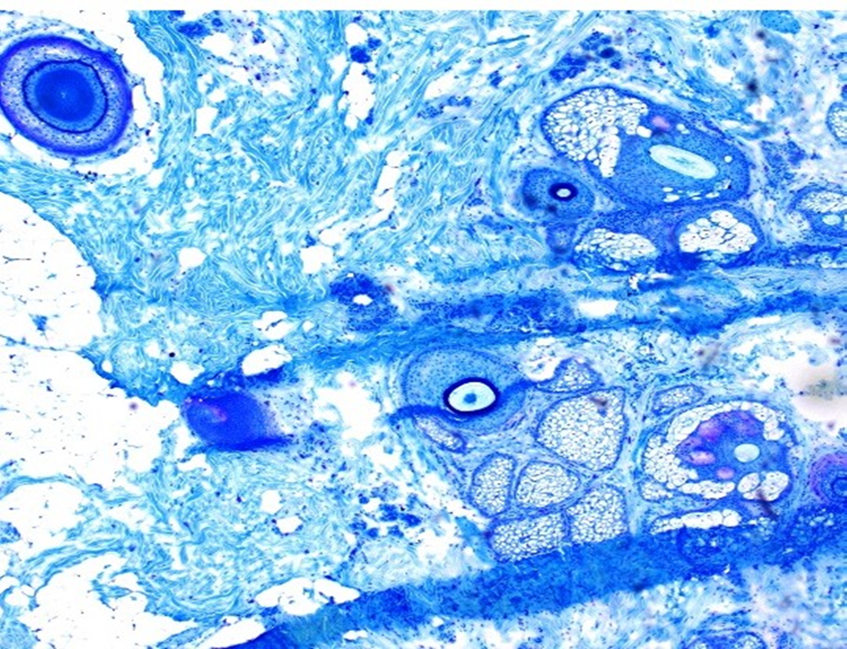

Martius Azul Escarlate

Este é um exemplo de lâmina corada com Azul Escarlate de Martius para demonstrar a presença de fibrina. Toda a fibrina deve apresentar coloração brilhante e ser distinguível de outras estruturas. Deve haver boa separação de cores entre os corantes para hemácias (amarelo), músculo (vermelho) e colágeno (azul). A coloração nuclear deve ser azul-escura ou preta. Este é um excelente exemplo com pontuação 10/10.